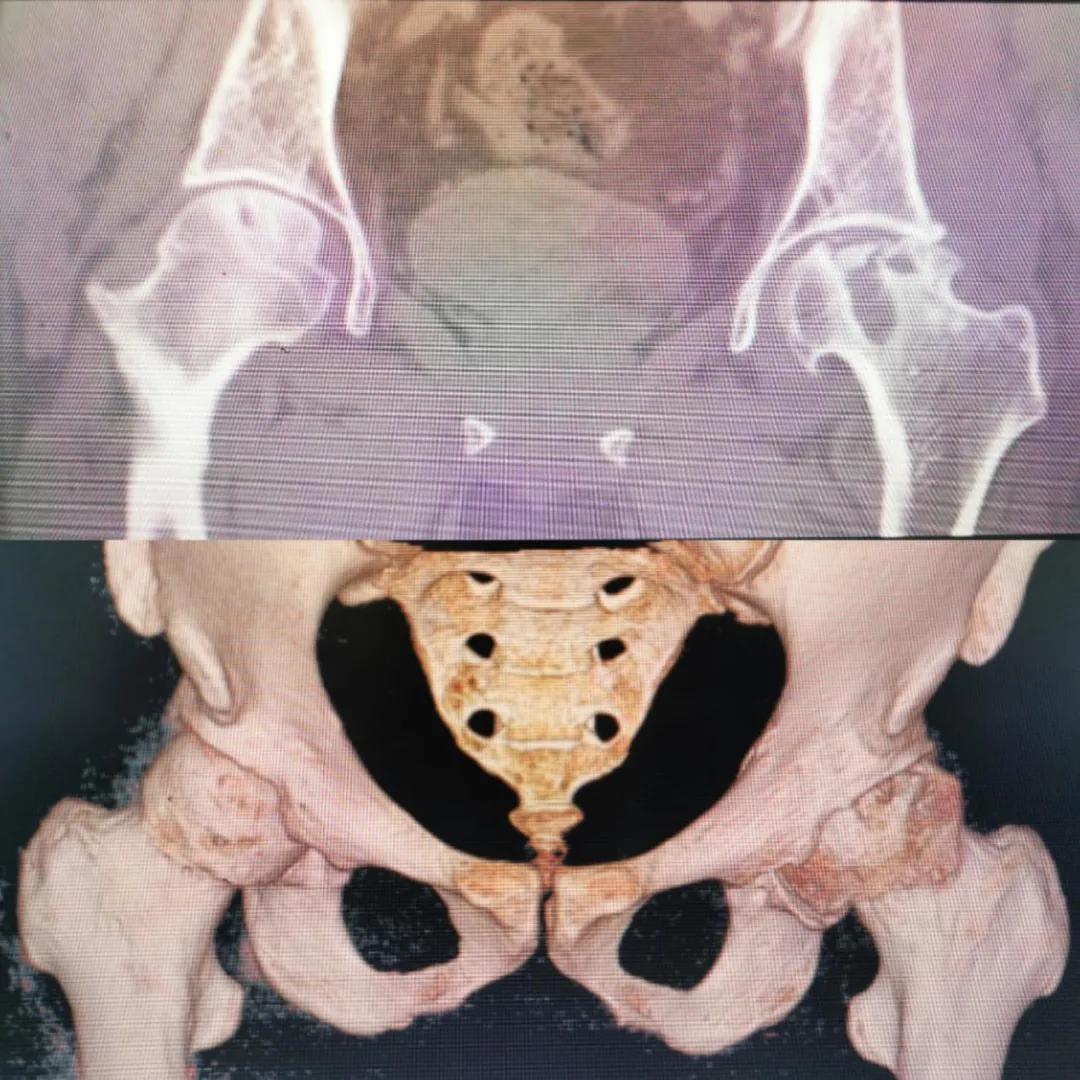

圖片(圖為患者入院時髖部CT檢查)

入院急查血結果提示炎癥反應,感染較重,凝血功能及肝功均不同程度損害;髖關節磁共振(MRI)檢查提示雙側股骨頭缺血壞死,繼發髖關節炎,左側髖周軟組織腫脹。醫療團隊給出的初步診斷為膿毒血癥、股骨頭缺血性壞死、軟組織感染、皮膚潰瘍及閉孔神經損傷。

追溯病史,患者訴前不久曾用蜂蜇療法治療股骨頭壞死,每日4次,每次100只蜜蜂蜇雙臀部、髖部,這才導致了病情急劇進展。查明了來龍去脈,我院智能微創骨科醫護團隊與患者家屬積極溝通病情,給予特殊級抗生素抗感染以及消腫、止痛等支持治療,同時對潰瘍創面進行專業、規范的清創、換藥處理,保護創面降低感染程度;護理上輔助翻身,減少壓力性損傷。